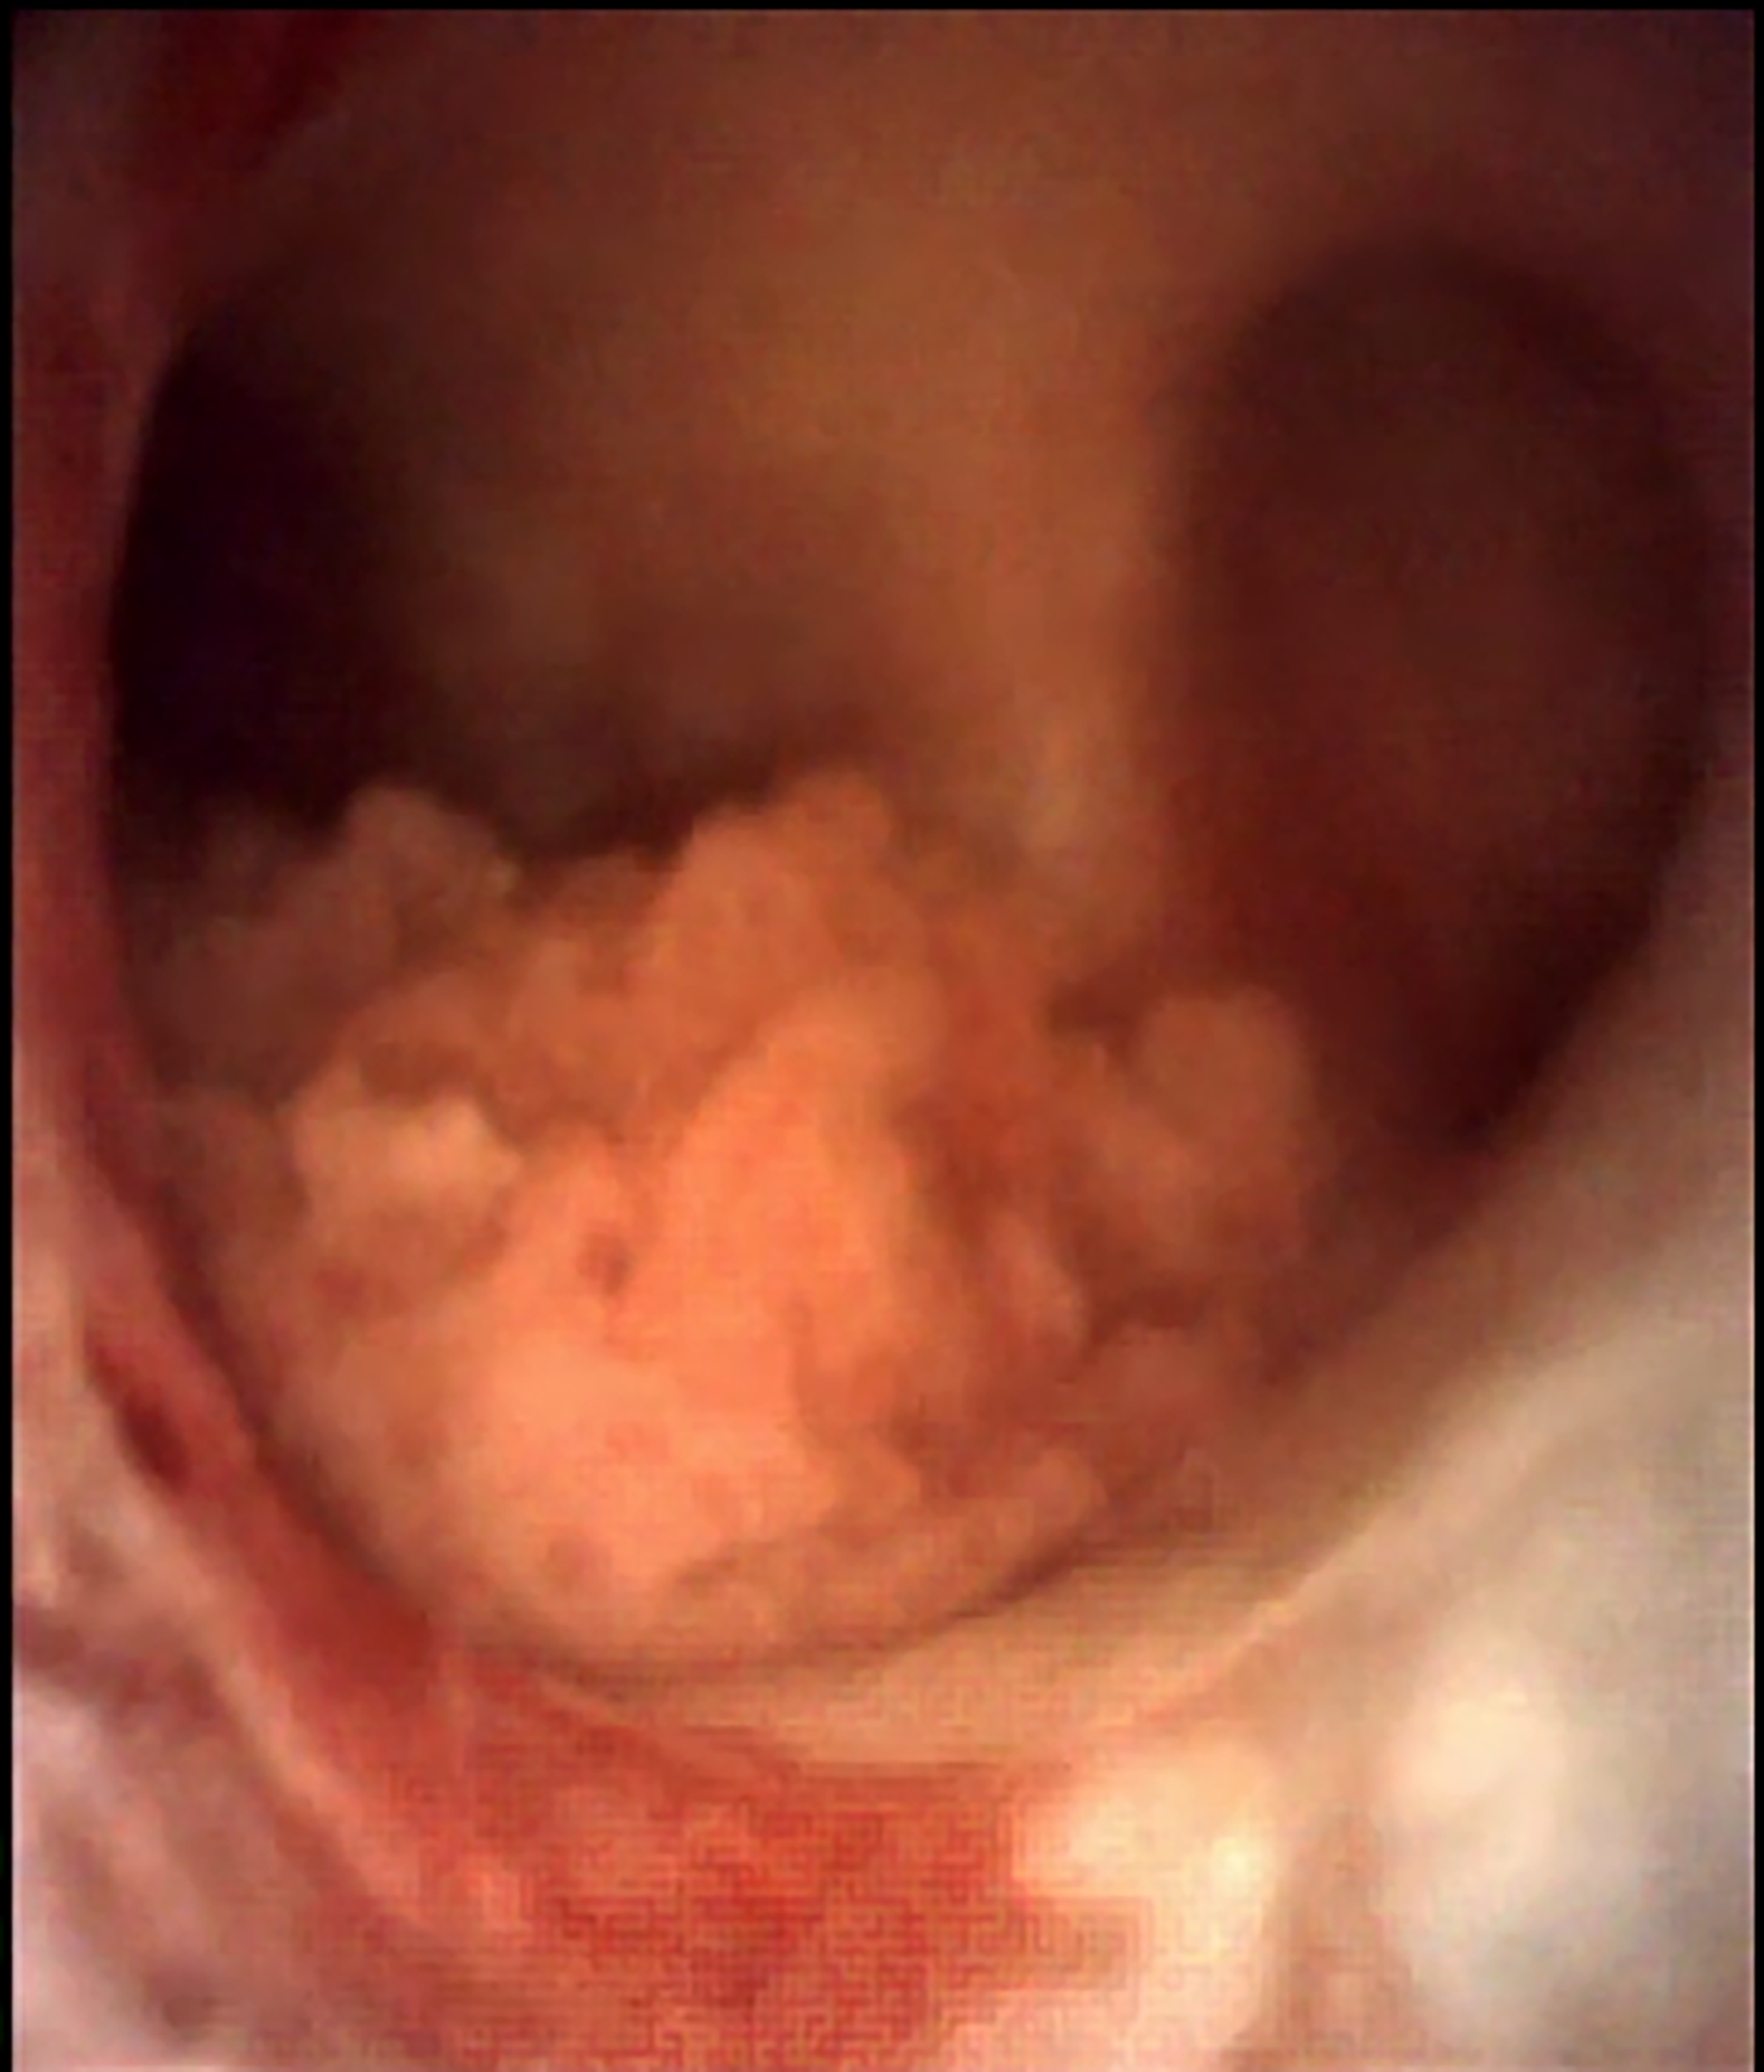

La técnica de URS flex para el diagnóstico de CVUA merece algunas consideraciones especiales. Cada vez que sea posible debería intentarse una inspección inicial «sin tocar» el uréter previamente. Es decir, sin introducir una guía hasta la pelvis renal antes de iniciar la ureteroscopía. Esto permite visualizar lesiones a lo largo de todo el uréter y en el sistema colector intrarrenal sin artefactos o hemorragia potencialmente causados por la manipulación previa (Figura 3). Sin embargo, para acceder al tracto superior, suele ser necesario dilatar al menos el orificio ureteral y el uréter distal con un ureteroscopio semirrígido o un dilatador (secuencial, coaxial o balón) sobre una guía apenas insinuada para poder avanzar luego el instrumento flexible sin dificultad (Video URS «no touch«).

Fig. 3. Imagen endoscópica de CVUA de pelvis renal